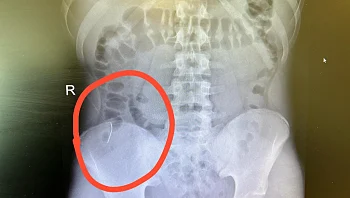

חשש לניקוב איברים פנימיים: נער בלע בטעות סיכה - חייו ניצלו בזכות הליך פולשני